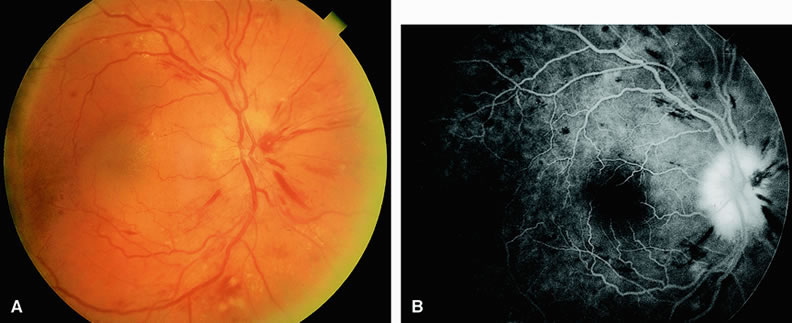

Ischemic central retinal vein obstructions generally reduce a patient's visual acuity to 20/200 or worse, most commonly to the counting-fingers or hand-motions range. Numerous cotton-wool spots and severe four-quadrant retinal hemorrhaging are often seen. Fluorescein angiography reveals confluent regions of retinal capillary nonperfusion (Fig. 11). Views of the posterior pole, as well as those of the four quadrants, may be necessary to demonstrate the capillary dropout. Magargal and associates12 quantitated the amount of retinal capillary nonperfusion in a posterior-pole 30-degree view in eyes with central retinal vein obstruction and calculated an ischemic index (area of retinal capillary nonperfusion/total area within the posterior 30-degree view). They found that when the index was 80% or greater, approximately 45% of eyes eventually developed rubeosis iridis and neovascular glaucoma.

Fig. 11. A. Fundus of a 35-year-old patient with an ischemic central retinal vein occlusion. The fundus has the classic “blood and thunder” appearance. Numerous intraretinal hemorrhages and retinal edema are present. The retinal veins appear dilated and tortuous. The optic nerve is swollen and hyperemic. B. Fluorescein angiogram of A shows fluorescence, indicating perfusion of the retinal arterioles. Filling of the tortuous retinal veins is delayed. Patchy areas of capillary nonperfusion indicating ischemia appear throughout the fundus.